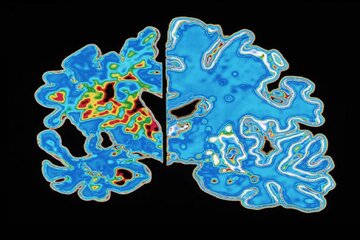

پروتئینهای تاو غیرطبیعی میتوانند رشتههای درهمتنیدهای تشکیل دهند که ارتباط میان سلولهای عصبی مغز را مختل میکند. آزمایشهای تصویربرداری مغزی که این تودههای درهم تنیده تاو را شناسایی میکنند، گاهی در تشخیص آلزایمر استفاده میشوند، و مطالعات اولیه نشان میدهد که چنین آزمایشهایی شاید بتوانند زمان بروز علائم آلزایمر را نیز پیشبینی کنند. اما شیندلر میگوید این روشهای تصویربرداری دشوار و پرهزینه هستند. در همین حال، پژوهشگران در حال بررسی آزمایشهای سادهتر مبتنی بر خون هستند که میتوانند تاو را نیز ردیابی کنند.